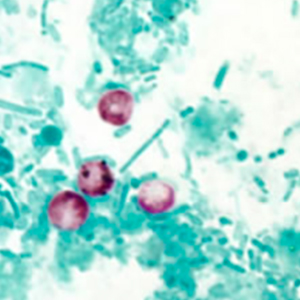

Cryptosporidium oocysts do not stain with Lugol. They are small, round, refringent structures measuring 4 to 6 µm in diameter. Their content cannot be visualized using optic microscopy. Their identification requires a modified Ziehl-Neelsen stain, which stains the parasites, that appear red to pink on a blue to green background. It is impossible to distinguish species of Cryptosporidium without molecular biology (Hoffman, 2017).